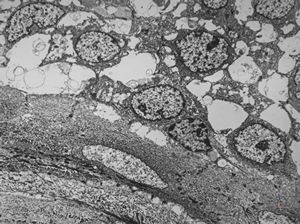

F,41y. | synovial metaplasia - capsule of implantate